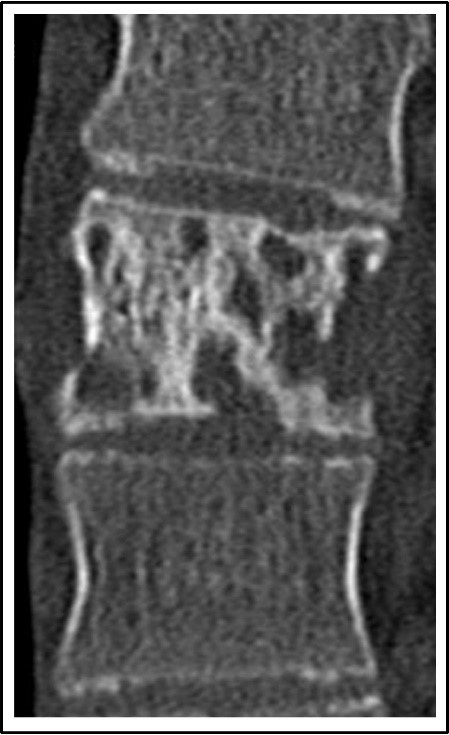

Abb. links: MRT einer Lenden- und Brustwirbelsäule. Der helle Herd zwischen dem 11. und 12. Brustwirbelkörper (gelbe Zahlen) signalisiert eine Wasseransammlung als Ausdruck einer bakteriellen Entzündung.

Abb. mitte: Das entsprechende CT stellt den Knochen und somit die fehlende Knochensubstanz am Entzündungsherd dar.

Abb. rechts: Röntgenkontrolle nach operativer Versorgung. Der Entzündungsherd wurde beseitigt und mit einem Platzhalter aufgefüllt. Vom 9. Brustwirbelkörper auf den 1. Lendenwirbelkörper wurde die Wirbelsäule stabilsiiert.